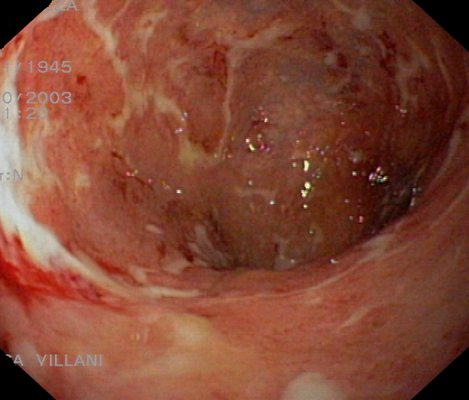

肛門癌圖片

肛癌早期症狀